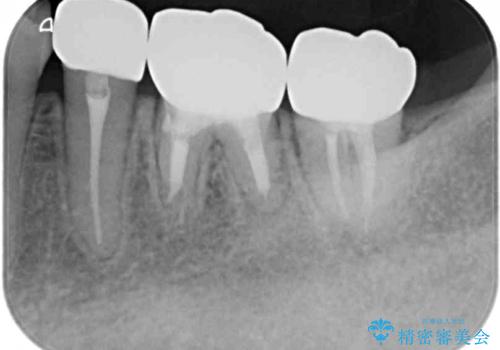

まだ銀歯が残っていますが、大きく目立つ銀歯をセラミックに置き換えることができ、人前で口を開けることを気にしなくなりました。

補綴治療中の後戻り対策をしっかりと行ったことで、歯列全体をきれいに整えることができました。